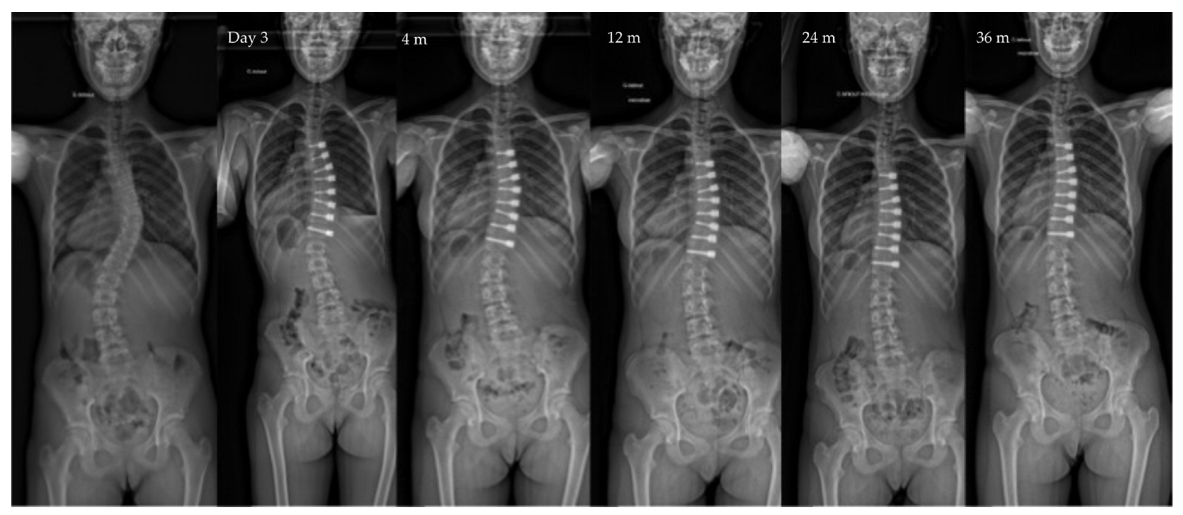

| Pre-op | Post-op Day 3 | Post-op 1y | Last f/u | p-Value | |

|---|---|---|---|---|---|

| Major curve | 49°(8,9°) | 27°(12°) | 22°(12°) | 19°(14°) | <0.01 |

| Secondary curve | 27°(14°) | 23°(15°) | 22°(11°) | 17°(10°) | <0.01 |

| Instrumented curve | NA | 26°(11°) | 23°(10°) | 20°(14°) | <0.01 |

| Kyphosis (T1–T12) | 20°(13°) | 23°(13°) | 25°(12°) | 24°(14°) | 0.06 |

| Lordosis (L1–L5) | 36°(12°) | 32°(13°) | 40°(7°) | 40°(8°) | 0.07 |